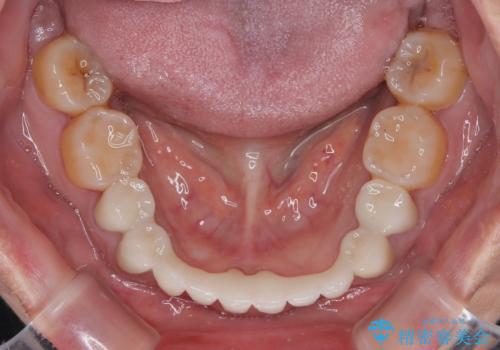

- 常に外れている下顎のブリッジと、前歯のデコボコと色を気にして来院された患者様です。

前歯のデコボコおよび奥歯の咬み合わせを改善するために、上顎左右の小臼歯を欠損スペースを利用して歯列を整え、矯正治療後に気になる上下前歯などをオールセラミッククラウンで美しく仕上げていくこととしました。

色や歯列が整ったことはもちろん満足いただけましたが、上顎の舌側転位していた前歯が綺麗に整ったことで違和感が減ったことを非常に喜んでいらっしゃいました。